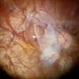

- Moahmed A,Tawfik MD , FRCSed

- Fundus camera

- Fundus Photo Of a case of Sub-total RD macular ON BCVA 1.0; demonstrated demarcation line denote old RD.